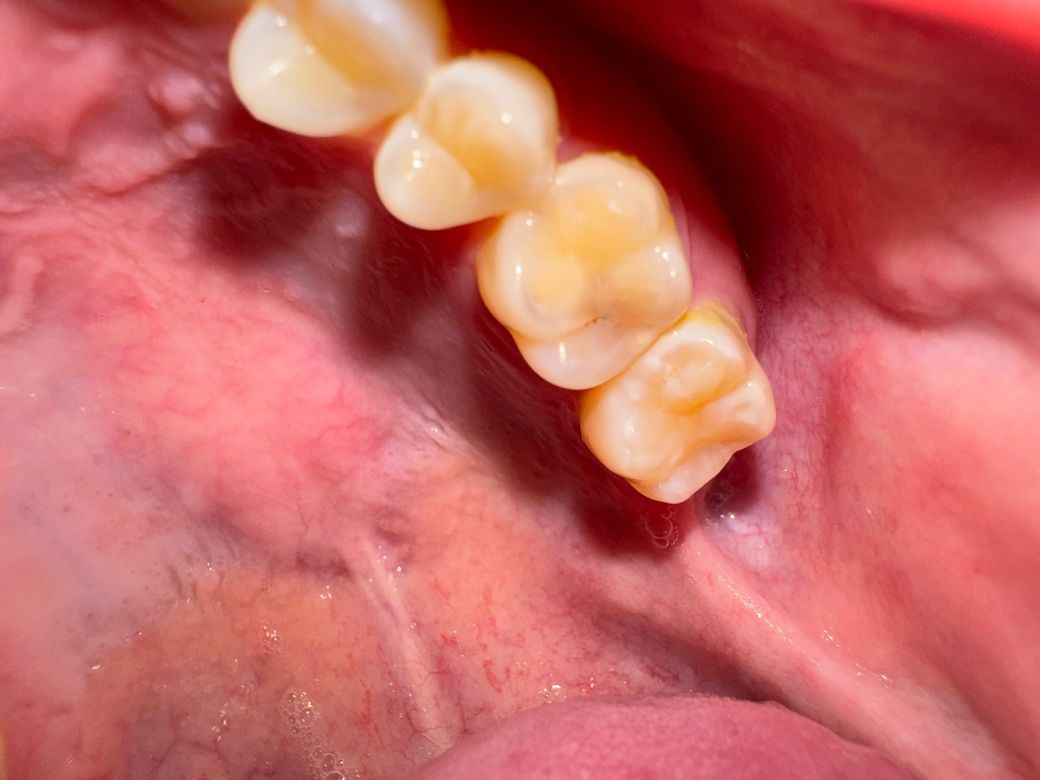

각각 상부 왼쪽 2번째 어금니, 하부 오른쪽 2번째 어금니입니다. 뭔가 까맣게 보이는 것 같아 충치인지 의심되는데 충치일까요? 또 충치라면 치료가 필요한 정도인가요?

-> 충치가 심해보입니다.

위에 사진은 충치가 안쪽으로 깊어 보이니 치과에 가셔서 엑스레이를 찍어보시고 검진을 받아보시는게 좋을것같습니다.

사진상 치아 2개다 충치가 맞는것 같고 초기충치로 보입니다 다만 엑스레이찍고 확인해봐야합니다

사진으로 봤을 경우에는 충치의 가능성이 있어보입니다.

치아 내부에 큰 충치가 있어도 치아 표면에는 작은 홈으로 보이는 경우도 있기때문입니다.

자세한 확인을 위해서 치과에서 진료를 받아보는 것을 권유드립니다.